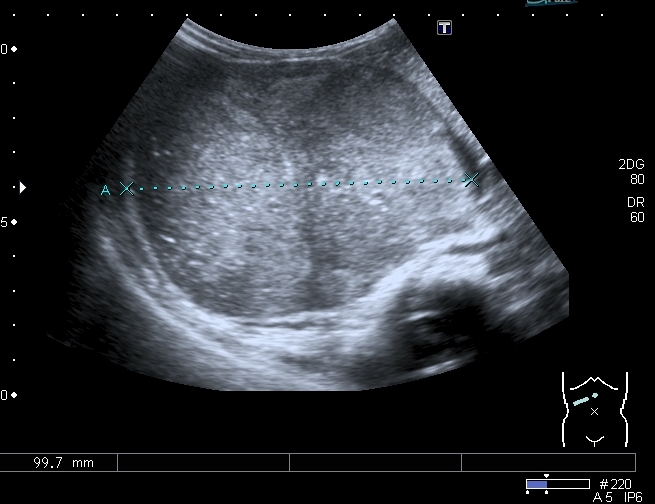

При УЗИ вся правая половина живота выполнена солидно - кистозным образованием больших размеров.

Правая почка нашлась в полости таза, верхним полюсом прилежала к образованию, но не была с ним связана.